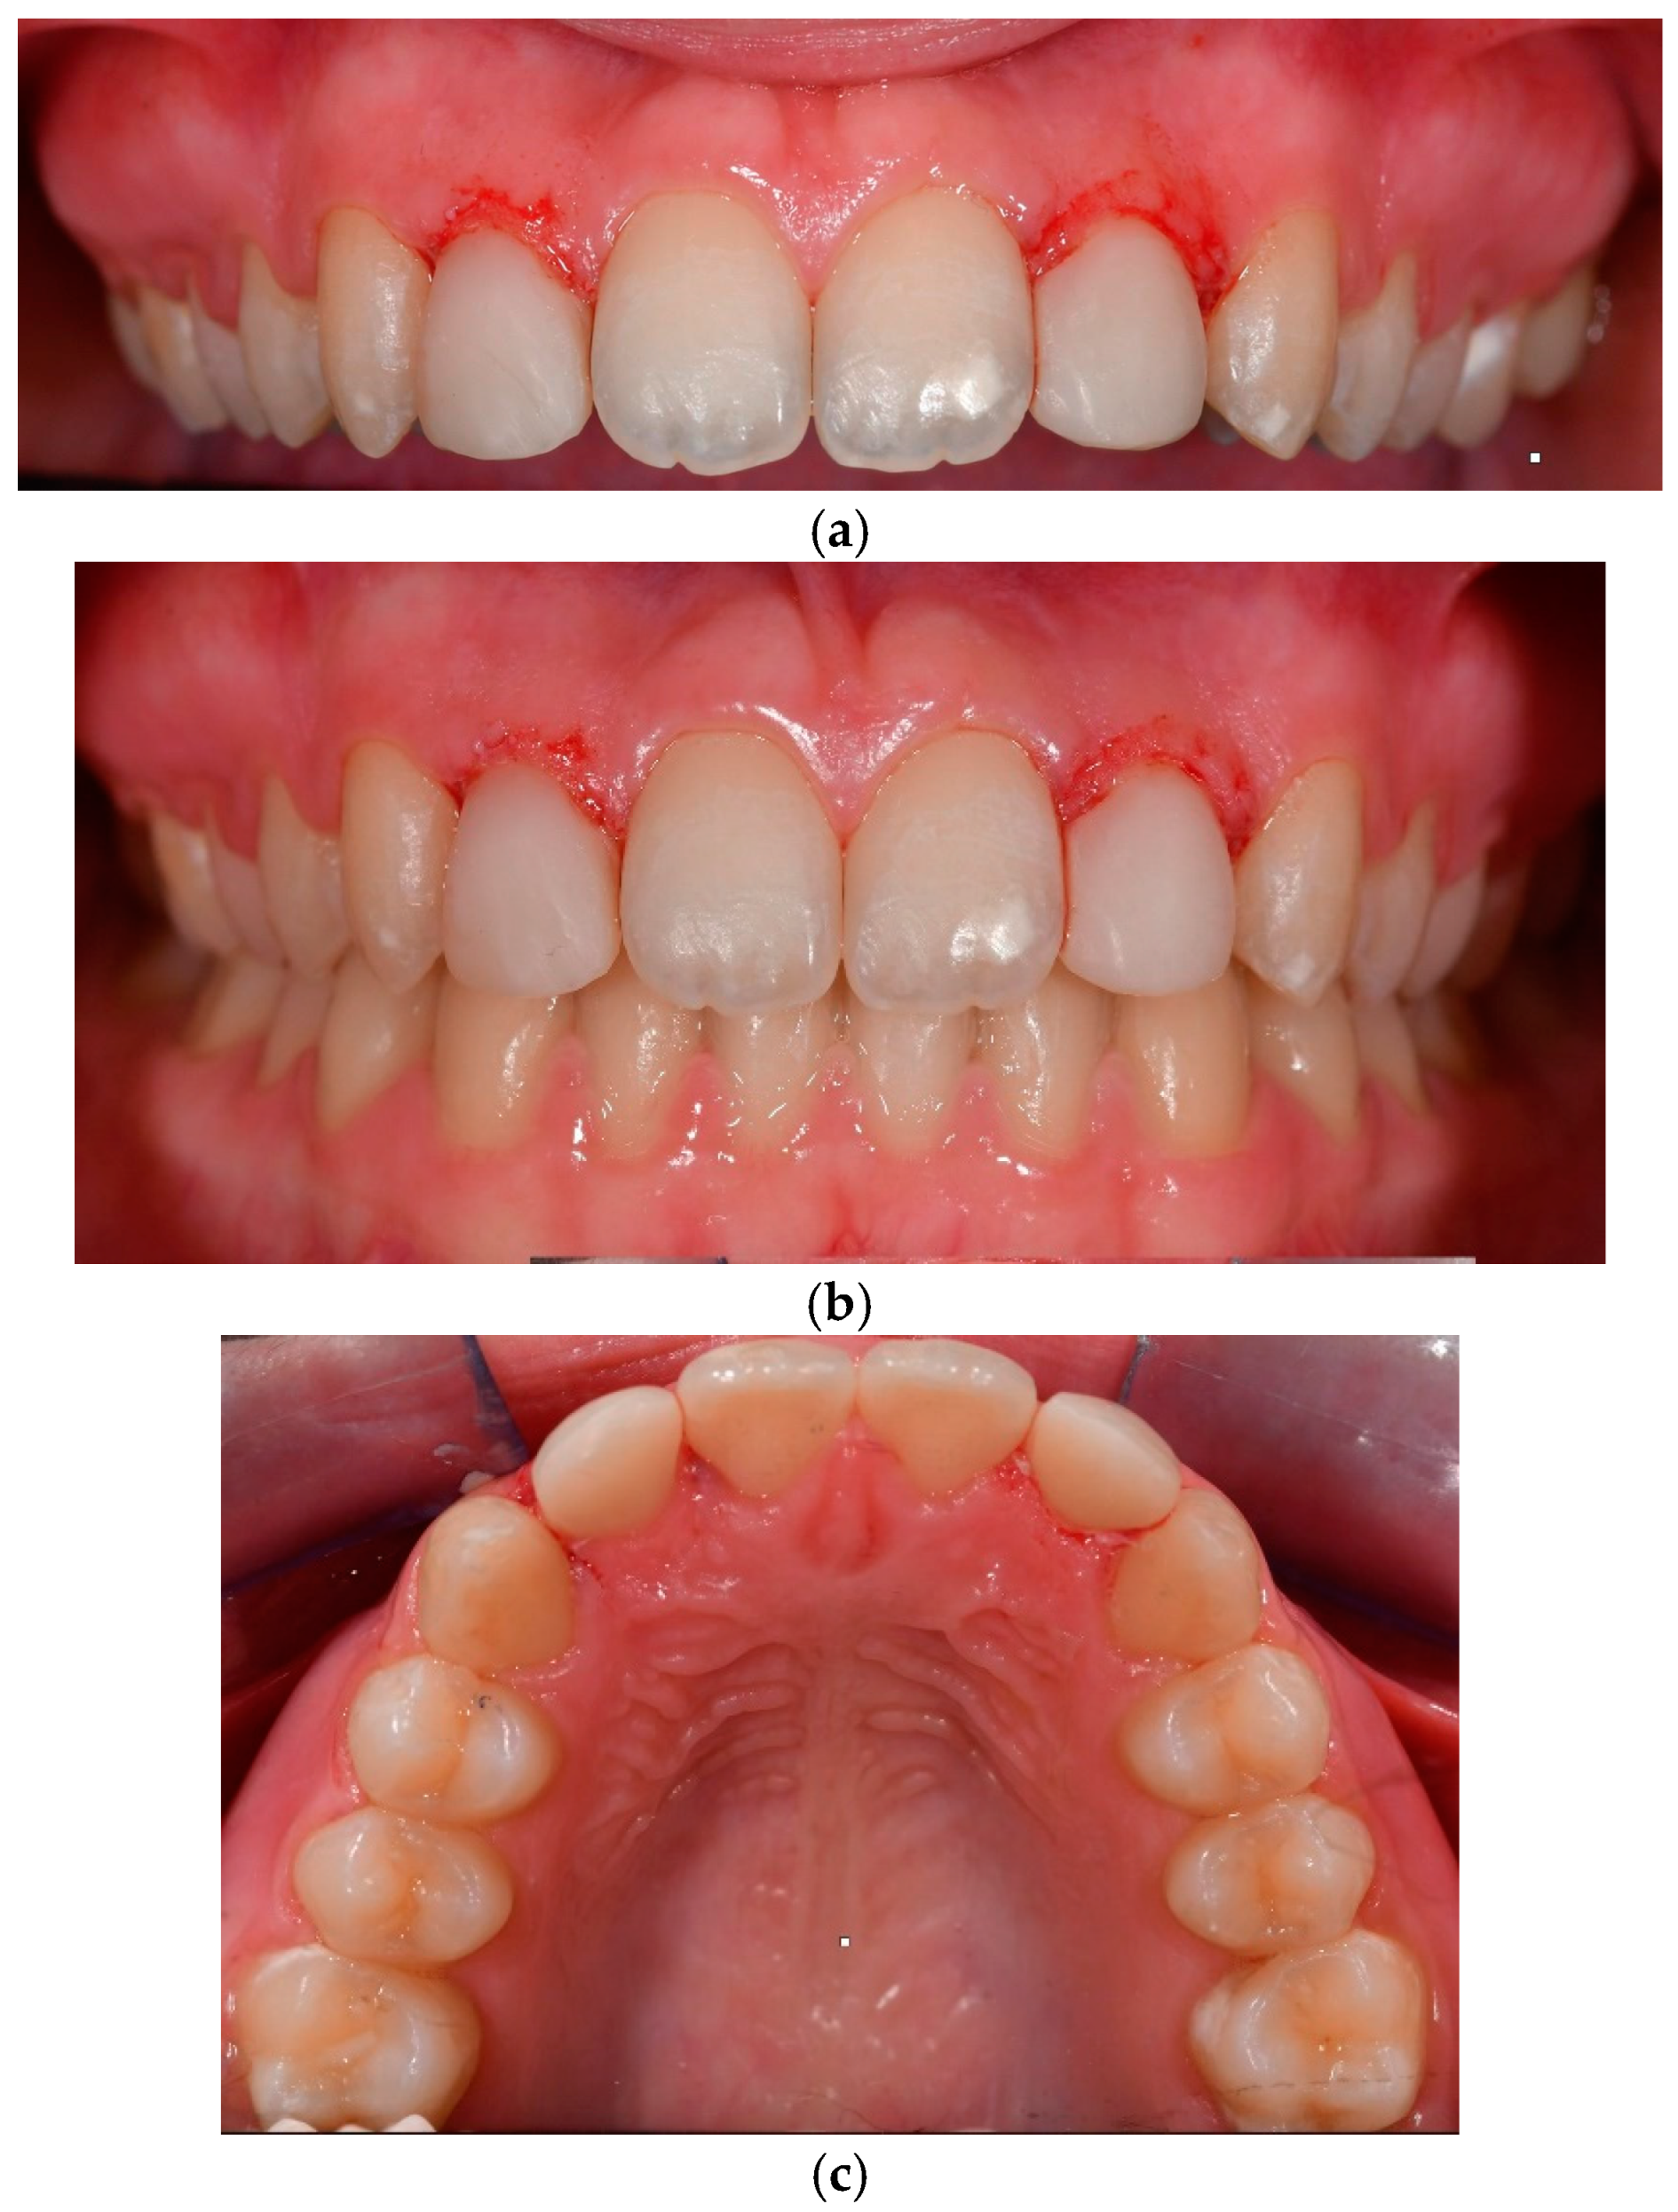

Figure 5.

(a) Detailed reshaping of teeth 12 and 22. (b) Frontal view of final occlusion. (c) Occlusal view to highlight the palatal aspect of the reconstructions on 12 and 22.

A six-month post-treatment evaluation revealed no signs of gingival inflammation, preserved periodontal health, and stable colour retention of teeth 12 and 22. The patient exhibited high tolerance and acceptance of the procedure. A six-year follow-up examination demonstrated no bleeding, physiological probing depths, healthy periodontal conditions, and satisfactory oral hygiene (Figure 6).

Figure 6.

Frontal view of final occlusion in a six-year follow-up control.